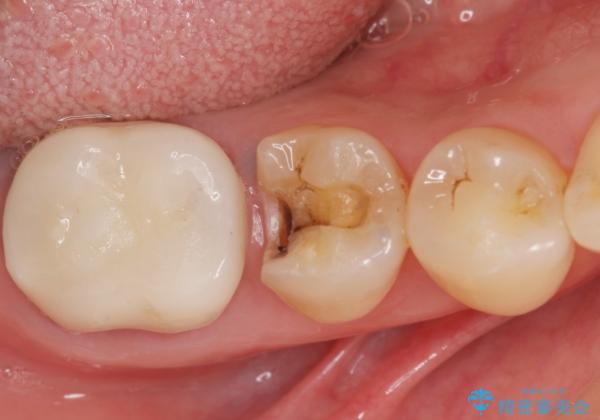

- 銀歯がしみることを主訴に来院されました。

(以前、当院で矯正と補綴治療を行った患者様です。→https://seimitsushinbi.jp/case/9774/ )

銀のつめものを除去したところ、大きなう蝕を認めました。